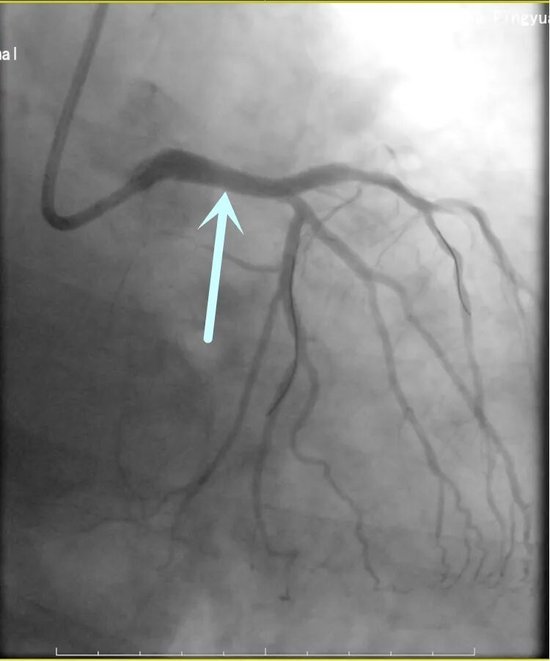

61岁的李阿姨因“胸闷1天,加重1小时”紧急入院,确诊为急性下壁心肌梗死。心内科介入团队迅速响应,一键启动导管室。急诊冠脉造影显示:冠心病三支病变——这意味着患者的三条主要血管均存在严重狭窄或闭塞,病情极为危重。

面对复杂病变,介入团队凭借丰富经验,迅速锁定“罪犯血管”右冠状动脉。在纤细的血管腔内,导丝精准通过闭塞段,球囊扩张、支架植入一气呵成。术后造影显示,血流瞬间恢复畅通,患者胸痛症状随即缓解。这场手术的成功,不仅体现了团队的应急反应速度,更考验了术者在多支病变中准确判断责任血管的“火眼金睛”。